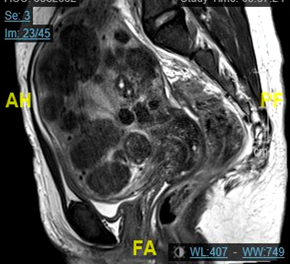

A 30-year-old nulliparous female presented to the emergency room with a chief complaint of abdominal discomfort, shortness of breath, and significant abdominal distension. On three prior occasions spanning 4 months, and prior to the Gynecology team being consulted, she was found to have severe ascites. Approximately 4 liters of benign serous fluid was drained each time via paracentesis. Cytology yielded benign pathology. She had no complaints of fevers, weight loss, or other constitutional symptoms, and had no recent travel history. She had no other significant past medical, surgical, or family history. On physical examination, she was distraught, tachypneic, and her abdominal exam showed distention, a fluid wave, and a 20-week fibroid uterus. EKG and echocardiogram were normal. Liver function and CA-125 tests were normal, and a screen for systemic lupus erythematosus was negative. Quantiferon testing was also negative. CT scan showed a large 20cm fibroid uterus and large ascites with no pleural effusion or other findings, and an MRI of the pelvis demonstrated “innumerable” uterine fibroids. It was explained to the patient that her presentation did not fit classic criteria for a specific disease, but that it could be related to her leiomyomas. After extensive counselling, she consented to an exploratory laparotomy with possible abdominal myomectomy. Intraoperatively, a complete survey showed no other abdominal pathology. 35 uterine leiomyomas were resected (largest measuring 6x5cm) and 2 liters of ascitic fluid were removed. Frozen pathology demonstrated benign leiomyomas. A JP drain was placed to monitor output. The production of peritoneal fluid was minimal during her hospital stay, and she did not re-accumulate any ascites more than one year post-operatively. The final pathology showed benign leiomyomas weighing 498g, and the abdominal fluid cytology was benign (Figure 1A) (Figure 1B).

Figure 1B MRI showing leiomyoma involving the entire uterus, and multiple areas of cystic degeneration.